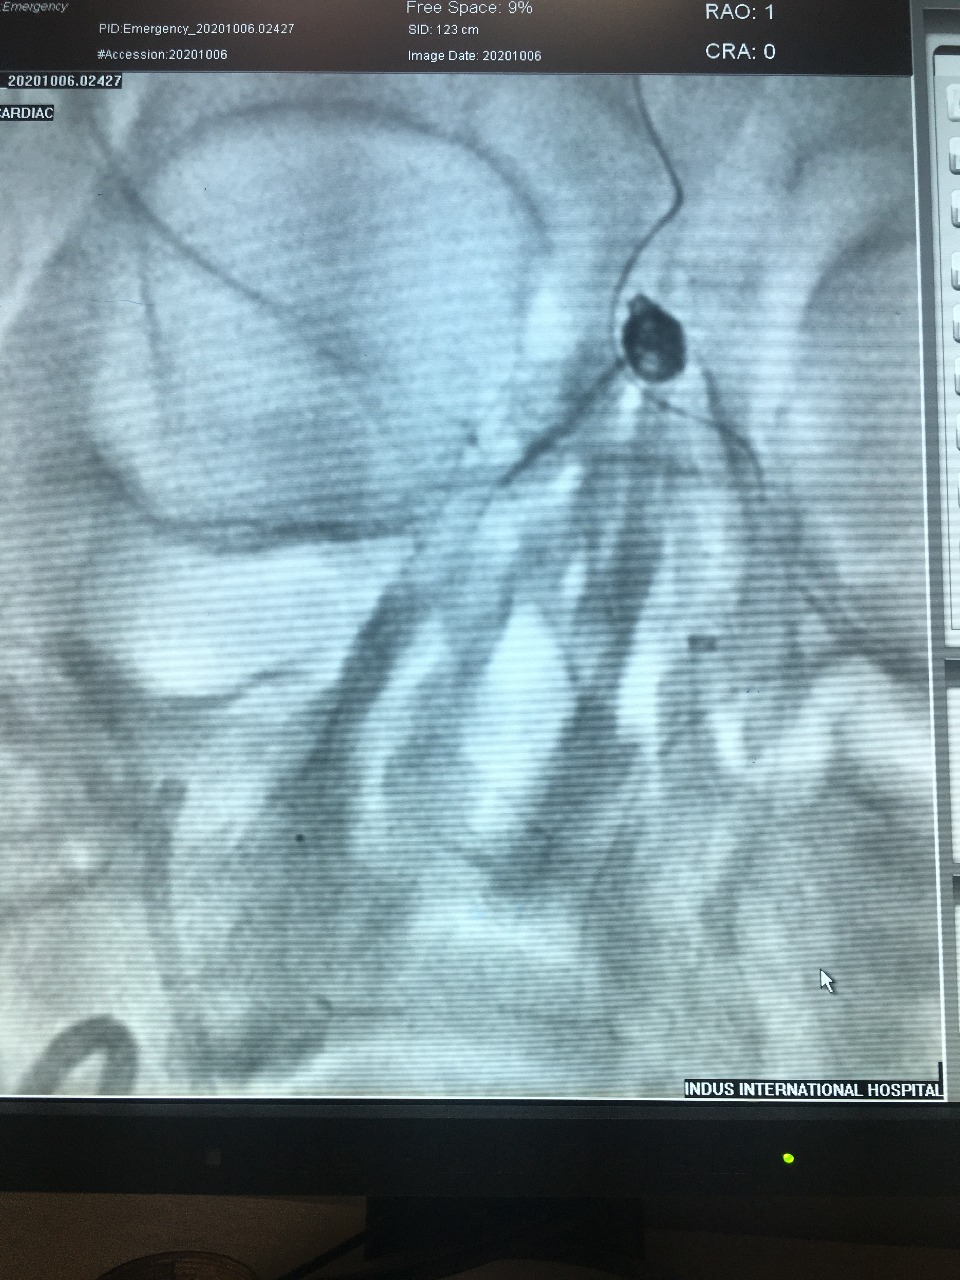

Aneurysm Coiled Successfully